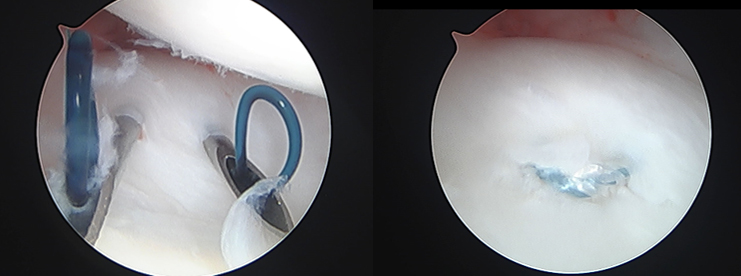

手術

手術は関節鏡視下TFCC縫合術(TFCC関節包縫合術、経骨孔TFCC縫合術)、手関節鏡視下デブリドマン、TFCC再建術、尺骨短縮骨切り術、鏡視下尺骨遠位端部分切除(Wafer procedure)などがあります。各術式は年齢、性別、利き手側、スポーツや活動レベル、受傷機転、罹病期間、症状、身体所見などの他、画像評価によるTFCCの状態や突き上げ症候群の有無、DRUJの状態など総合的に評価して決定していきます。手術後は3~6週間、外固定を行います。また、リハビリテーションを行います。状態次第ですが、術後3~6か月程度で日常生活動作やスポーツ復帰が可能となります。

【関節鏡視下TFCC関節包縫合術】